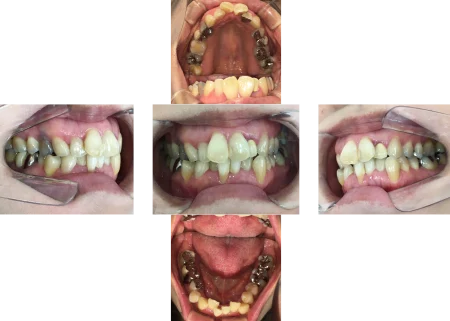

拝見すると、上の前歯が前方に出ている「上顎前突(じょうがくぜんとつ)」でした。

さらに、下左右の前歯6本(中切歯/1番、側切歯/2番、犬歯/3番)は、歯が重なり合って生えている「叢生(そうせい)」で、噛み合わせも悪くなっていました。

また、歯を支えている骨「歯槽骨」が減退する「歯周病」も認められました。

叢生を改善させるために、右下の前歯(中切歯)を抜歯してスペースを作る必要があることをご説明し、同意いただきました。

そして、歯並びを整えるために、取り外し式のマウスピース型矯正装置「インビザラインフル」を選択しました。

インビザラインフルは、前歯から奥歯まで全ての歯を動かすことができます。

歯を動かす際には、歯周病が悪化しないよう配慮しながら治療を行いました。